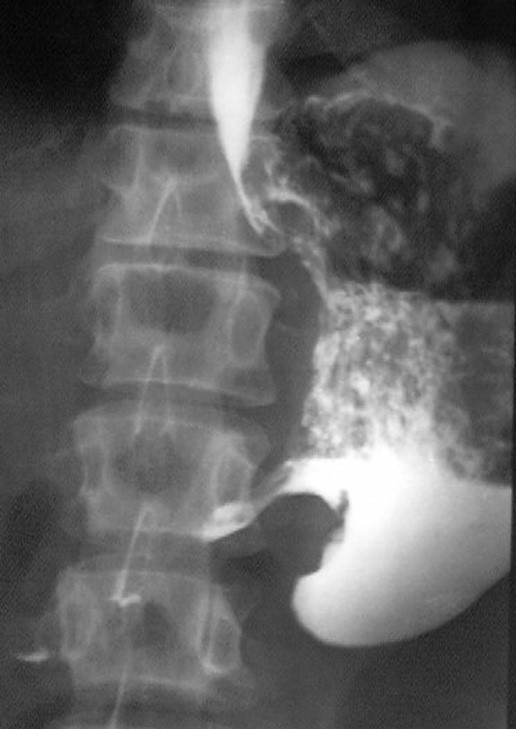

Rentgenologik tekshiruv: Ikki kontrastli oshqozon rentgeni (bariy suspenziyasi) antral boʼlimda oshqozon devorining notekisligini, "olma yadrosi" tipidagi toʼldirish nuqsonini koʼrsatdi. Devorlar qalinlashgan, peristaltika buzilgan. Qoʼshimcha KT-skanirovkada 5x4 sm oʼlchamdagi massa, atrofdagi toʼqimalarga invaziya, limfadenopatiya va jigar metastazlari shubhasi aniqlandi.

Muhokama: Oshqozon oʼsmalari rentgenogrammalarida toʼldirish nuqsonlari, devor qalinlashishi, prospekt suziqligi koʼrinadi. Yaxshi holatlardan (yara yoki polip) farqlash muhim. Erta belgilari mukoza oʼzgarishlari, kech belgilari infiltratsiya va metastazlar.